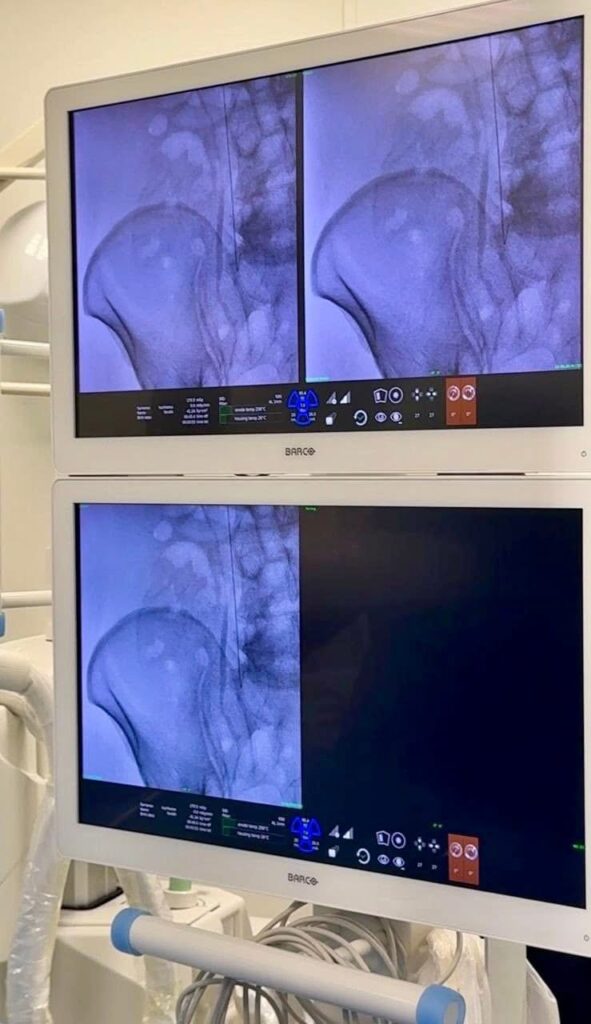

Асқынулардың алдын алу үшін дәрігерлер баллонды технологиямен үйлестірілген заманауи әдіс — тамырішілік ультрадыбыстық тромболизис қолданды. Процедура барысында тромб ішіне арнайы вибрациялық катетер енгізіліп, ол тромбты механикалық түрде ұсақтап, дәрілік заттардың тиімді әсер етуіне жағдай жасайды. Сонымен бірге, катетер арқылы қысыммен енгізілген тромболитикалық препарат тромбтарды ерітуге мүмкіндік береді.

Осындай кешенді тәсіл қысқа уақыт ішінде қан тамырларының өткізгіштігін қалпына келтіріп, өмірге қауіп төндіретін асқынулардың алдын алуға жол ашады.